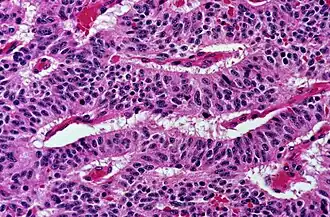

Cancellous bone is formed from groupings of trabeculated bone tissue. In cross section, trabeculae of a cancellous bone can look like septa, but in three dimensions they are topologically distinct, with trabeculae being roughly rod or pillar-shaped and septa being sheet-like.

Trabecular bone, also called cancellous bone, is porous bone composed of trabeculated bone tissue. It can be found at the ends of long bones like the femur, where the bone is actually not solid but is full of holes connected by thin rods and plates of bone tissue.[5] The holes (the volume not directly occupied by bone trabecula) is the intertrabecular space, and is occupied by red bone marrow, where all the blood cells are made, as well as fibrous tissue. Even though trabecular bone contains a lot of intertrabecular space, its spatial complexity contributes the maximal strength with minimum mass. It is noted that the form and structure of trabecular bone are organized to optimally resist loads imposed by functional activities, like jumping, running and squatting. And according to Wolff's law, proposed in 1892, the external shape and internal architecture of bone are determined by external stresses acting on it.[6] The internal structure of the trabecular bone firstly undergoes adaptive changes along stress direction and then the external shape of cortical bone undergoes secondary changes. Finally bone structure becomes thicker and denser to resist external loading.

Typically, the porosity percent of trabecular bone is in the range 75–95% and the density ranges from 0.2 to 0.8 g/cm3.[7] It is noted that the porosity can reduce the strength of the bone, but also reduce its weight. The porosity and the manner that porosity is structured affect the strength of material. Thus, the micro structure of trabecular bone is typically oriented and ''grain'' of porosity is aligned in a direction at which mechanical stiffness and strength are greatest. Because of the microstructural directionality, the mechanical properties of trabecular bone are highly anisotropic. The range of Young's modulus for trabecular bone is 800 to 14,000 MPa and the strength of failure is 1 to 100 MPa.

The compressive strength of trabecular bone is also very important because it is believed that the inside failure of trabecular bone arise from compressive stress. On the stress-strain curves for both trabecular bone and cortical bone with different apparent density, there are three stages in stress-strain curve. The first is the linear region where individual trabecula bend and compress as the bulk tissue is compressed.[6] The second stage occurs after yielding, where trabecular bonds start to fracture, and the final stage is the stiffening stage. Typically, lower density trabecular areas offer more deformed staging before stiffening than higher density specimens.[6]

In summary, trabecular bone is very compliant and heterogeneous. The heterogeneous character makes it difficult to summarize the general mechanical properties for trabecular bone. High porosity makes trabecular bone compliant and large variations in architecture leads to high heterogeneity. The modulus and strength vary inversely with porosity and are highly dependent on the porosity structure. The effects of aging and small cracking of trabecular bone on its mechanical properties are a source of further study.